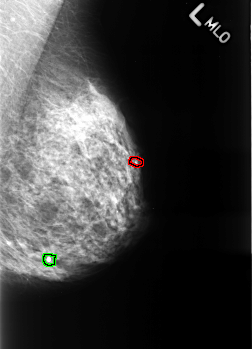

B_3251_1.LEFT_MLO

FILE: B_3251_1.LEFT_MLO.OVERLAY

TOTAL_ABNORMALITIES 2

ABNORMALITY 1

LESION_TYPE CALCIFICATION TYPE LUCENT_CENTER-PUNCTATE DISTRIBUTION N/A

ASSESSMENT 2

SUBTLETY 5

PATHOLOGY BENIGN_WITHOUT_CALLBACK

ABNORMALITY 2